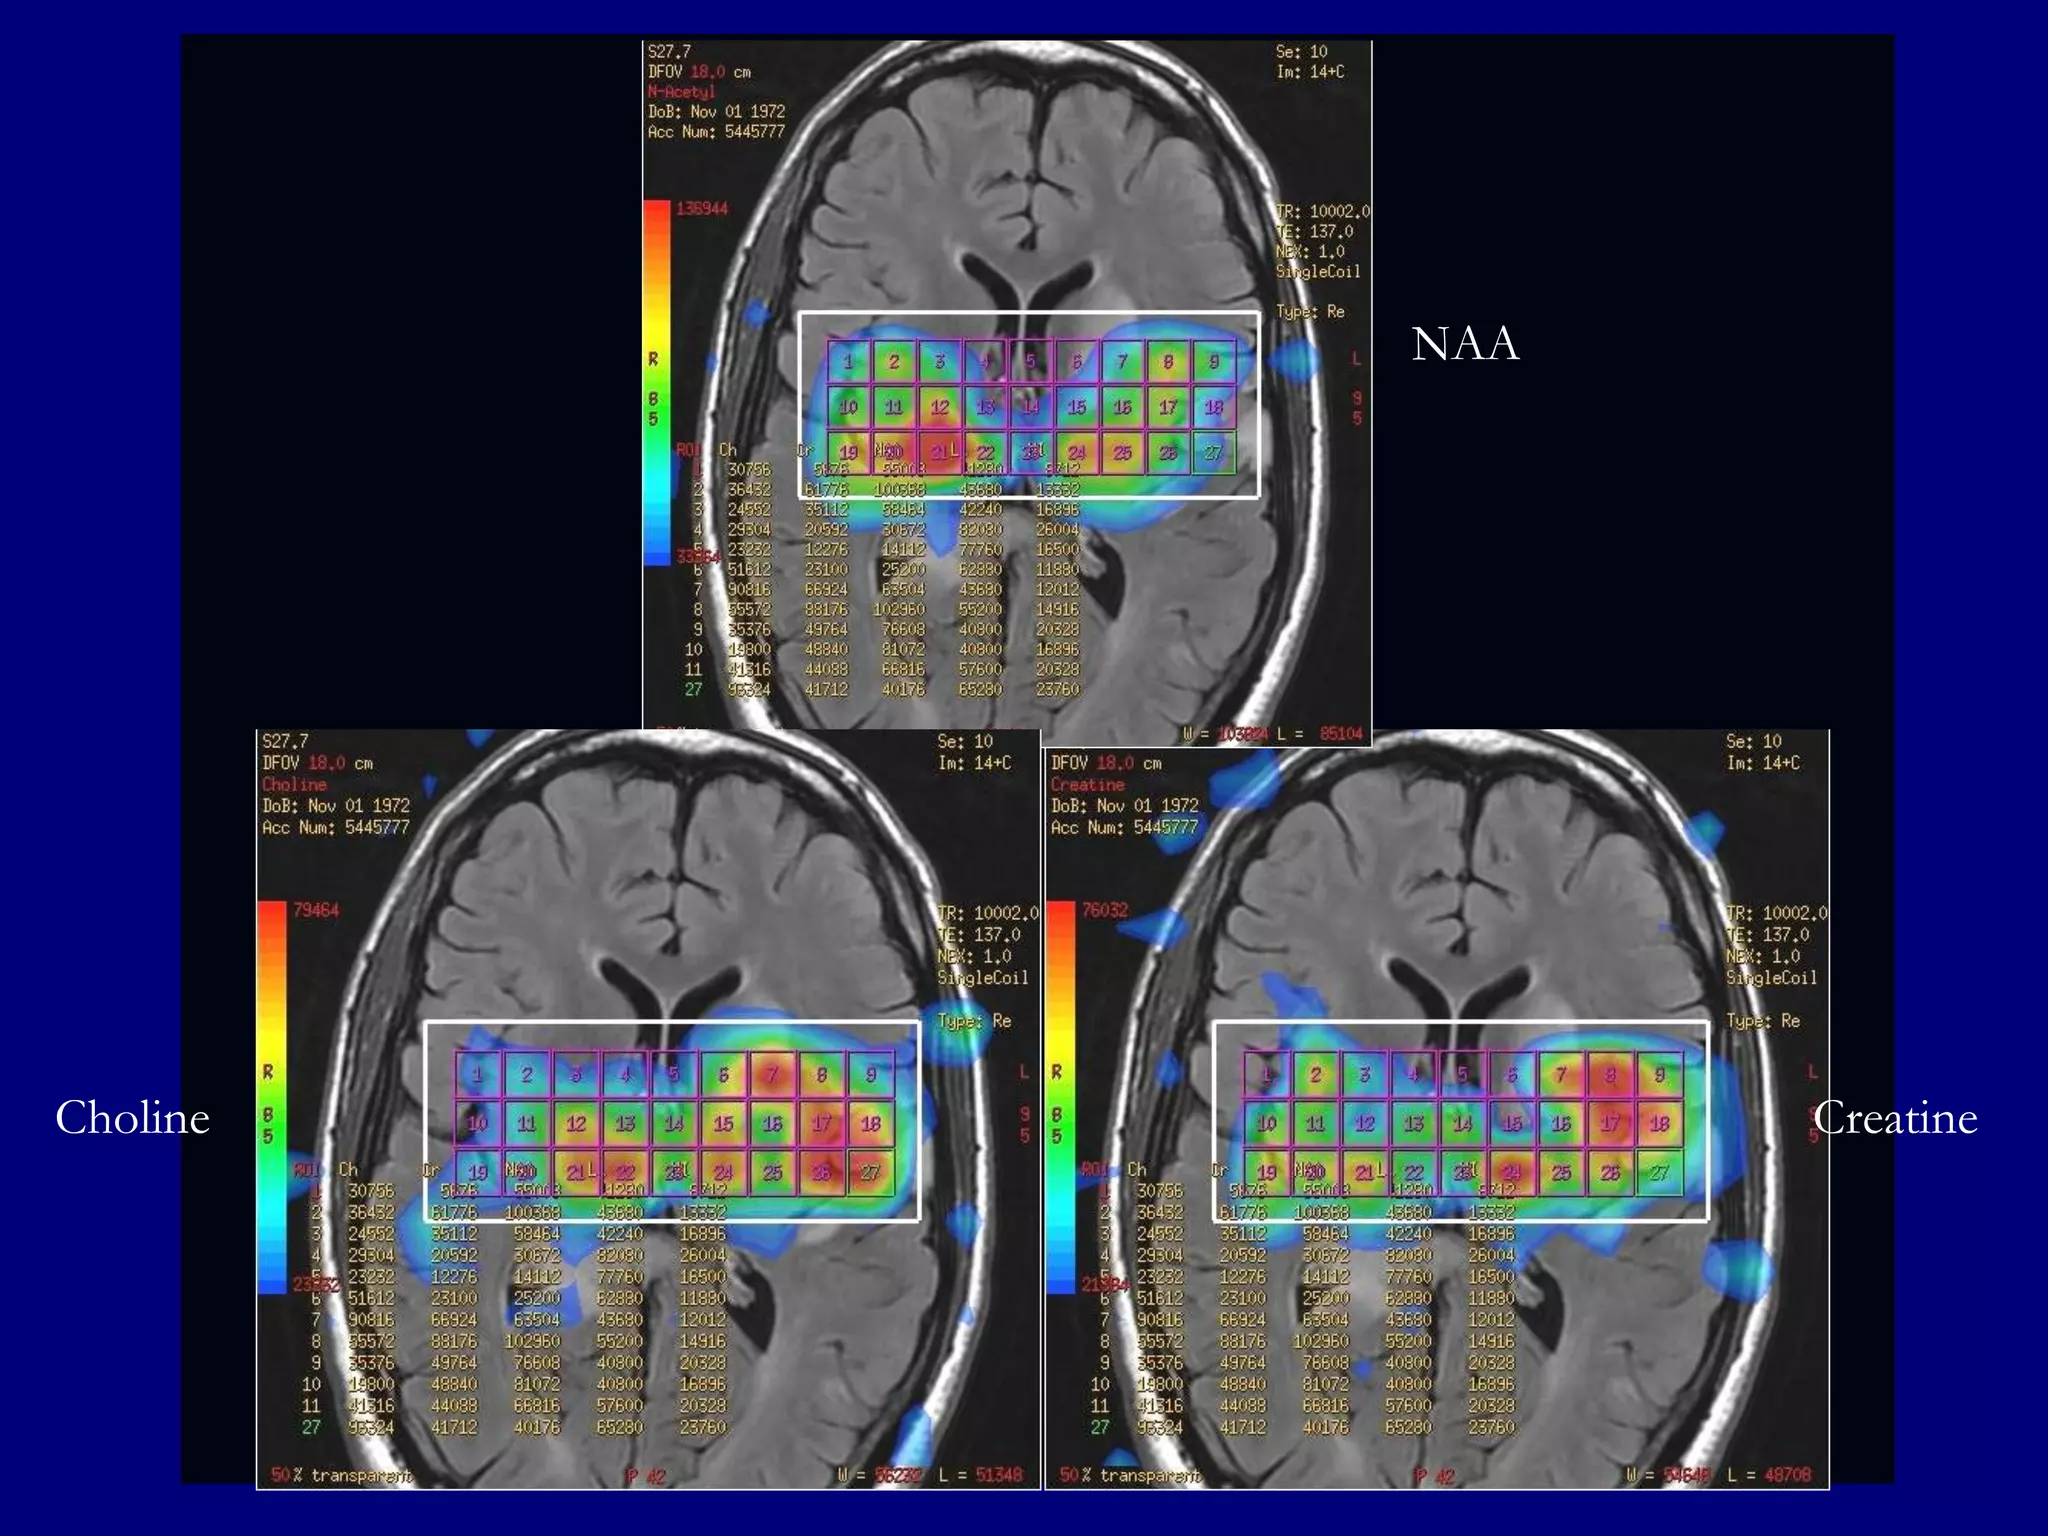

NAA

Choline

2D- CSI (PROBE: TE=144, Section=10mm, NEX=1

Creatine

MR Spectroscopy

Large Choline peak

 High choline/creatine ratio

 Lactate peak may be seen